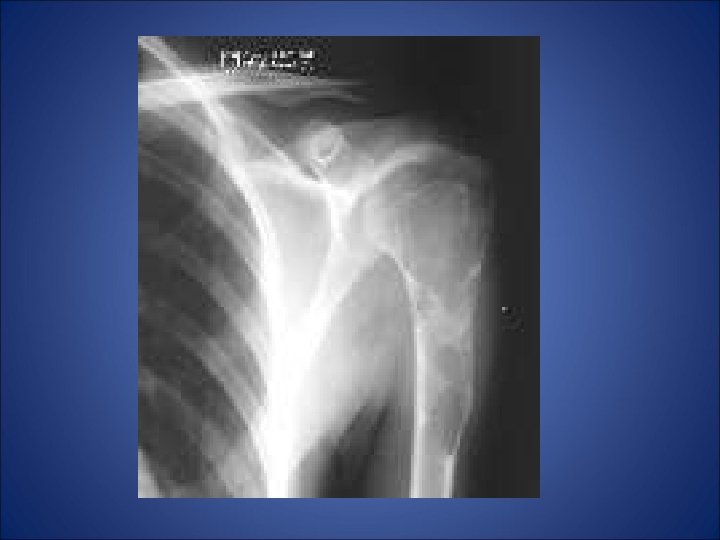

• A 26 yrs old male presented with complaint of pain in left shoulder after lifting a heavy weight. • His x-ray of left shoulder was taken which revealed…

Shows slightly expansile, septated lytic lesion is present involving the proximal 1 /3 rd of the left humerus. The margins are not sclerotic. The epiphysis appears uninvolved.

The most likely differentials would be: • Unicameral bone cyst • Aneurysmal bone cyst • Enchondroma • Fibrous dysplasia • Myxoid fibroma.

Radiolucent lesion with expanded cortex arising in medullary canal of metaphysis of humerus -aneurysmal expanded appearance of cortex is contained by periosteum & thin shell of bone; -Marked cortical thinning and erosion and periosteal elevation

• Thus in our case… • Metaphyseal expansile lytic lesion which is centrally located and a multiloculated appearance not involving epiphysis without any calcification with surrounding normal bone in the proximal end of humerus in a 26 yrs old male … • Mostly likely diagnosis is • UNICAMERAL BONE CYST